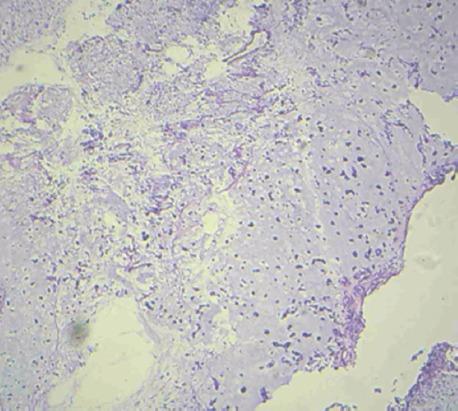

肩部骨外间叶性软骨肉瘤:1例极其罕见的病例

Extraskeletal Mesenchymal Chondrosarcoma of Shoulder: An Extremely Rare Case.

In the current paper, we introduced a 47-year-old Iranian male patient having painless, mobile, nontender, and firm mass in left shoulder. We did not find neurovascular disturbance at the upper extremity, and the patient had a full range of motion in the left shoulder. The tumor was treated with wide resection and followed by radiation therapy.

骨外软骨肉瘤(EMC)是一种罕见的侵袭性肿瘤,见于软组织区域。这种软组织肉瘤根据组织学标准分为黏液样和间充质型。间充质亚型预后较差。在大约50%的EMC患者中,我们可以在传统X线摄影中观察到软组织病变和点状钙化。

在本文中,我们介绍了一名47岁的伊朗男性患者,其左肩有一个无痛、可活动、无压痛且质地坚硬的肿块。我们未发现上肢存在神经血管紊乱,且该患者左肩活动范围正常。该肿瘤接受了广泛切除,随后进行了放射治疗。